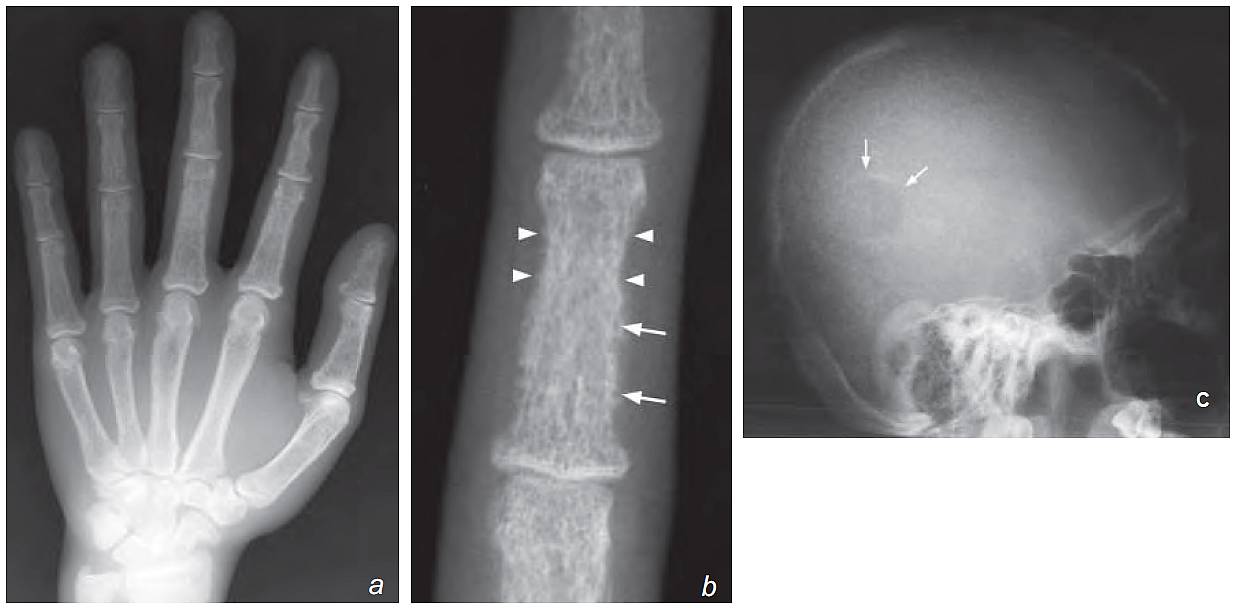

- Frontal view of hand:

- Generalized osteopenia

- Cortical bone tunneling

- Subperiosteal bone resorption

b) Magnifi ed view of the third middle phalanx shows a lace-like cortex due to bone resorption and enlargement of the Haversian canals (latter seen as the numerous holes in the cortex, [arrows]). There is also subperiosteal bone resorption (arrowheads).

- Subperiosteal outer cortical bone resorption – most prominent in middle phalanx of 2nd and 3rd fi ngers

- Cortical tunneling – bony resorption within Haversian canals of cortex.

- Lace-like appearance of bone cortex due to a combination of the above signs